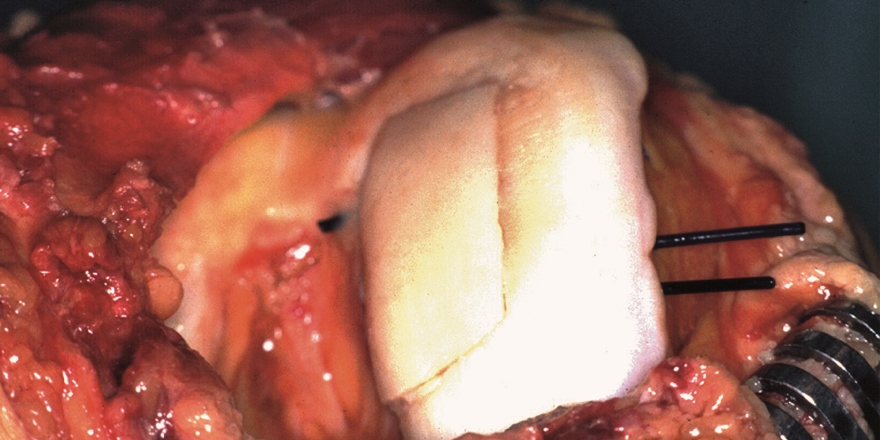

Ein Allograft ersetzt den beschädigten Knorpel. Ein Allograft ersetzt den beschädigten Knorpel. © J. Jerosch